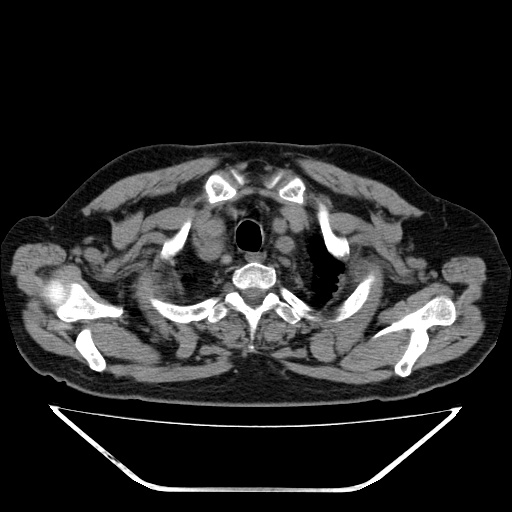

另胸椎旁改变考虑神经鞘瘤可能性大

1双肺转移性肺癌,2t12~l1右侧椎旁神经鞘瘤。

双肺多发转移瘤。纵隔淋巴结肿大。胸椎右旁软组织结节,考虑神经源性肿瘤,请进一步检查。

胸椎旁软组织密度影,与椎管内结构相连,相应椎间孔开大,考虑为神经源性肿瘤(神经鞘瘤)可能

1双肺及纵隔淋巴转移性病变,2t12~l1右侧椎旁神经鞘瘤。

支持 1、双肺转移瘤伴纵隔淋巴结肿大 2、右侧椎旁神经鞘瘤可能性大

胸椎右旁软组织结节,考虑神经源性肿瘤。